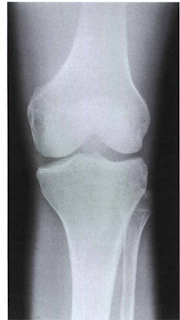

Gambar